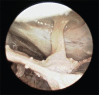

Figure 6

Following the opening of the chiasmatic cistern, diaphragma sellae and infundibulum were exposed with the use 30 degree lense endoscope